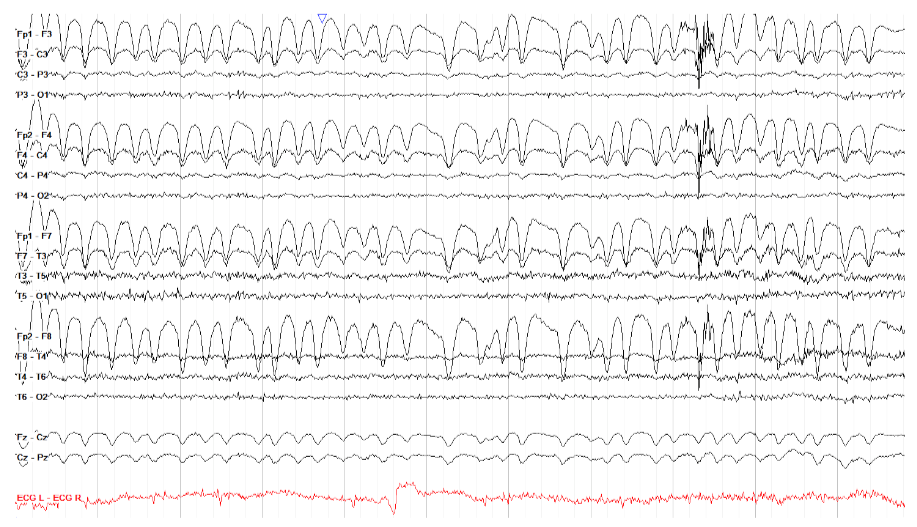

③ 胸部物理治疗伪影(Chest physiotherapy artifact)

在医院,特别容易发生在 ICU 中接受插管和镇静的患者中,因为它可能看起来像癫痫发作一样有节律,但通过观看视频(如果有)可以轻松区分这两者(即使没有敏锐的电生理技能)。

在脑电图上,它通常也与癫痫发作不同,因为它缺乏场或演变。胸部 PT 往往在后方更加突出,但根据患者的位置和 PT 的应用位置,情况可能会有很大差异。